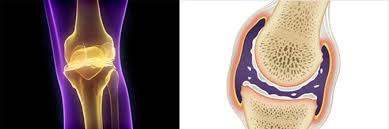

무릎 연골 손상 증상을 진단하기 위해서는 전문의의 상담과 검사가 필요합니다. X-ray나 MRI와 같은 진단 방법을 통해 손상의 범위와 정도를 확인할 수 있으며, 이는 적절한 치료 방법을 결정하는 데 중요한 역할을 합니다. 초기 진단이 이루어지지 않으면 무릎 연골 손상 증상이 악화되어 퇴행성 관절염으로 이어질 가능성이 높기 때문에, 무릎 통증이 지속되면 즉시 의료기관을 방문해야 합니다.

무릎 연골 손상 증상을 치료하는 방법은 보존적 치료와 수술적 치료로 나뉩니다. 경미한 손상의 경우 휴식, 물리치료, 주사 요법 등으로 회복을 시도할 수 있으며, 증상이 호전되지 않으면 수술적 치료가 필요할 수 있습니다. 수술은 손상의 정도에 따라 봉합술이나 절제술로 나뉘며, 이는 회복 과정에서 중요한 역할을 합니다. 모든 치료 방법은 전문의와의 상담을 통해 신중히 결정해야 합니다.